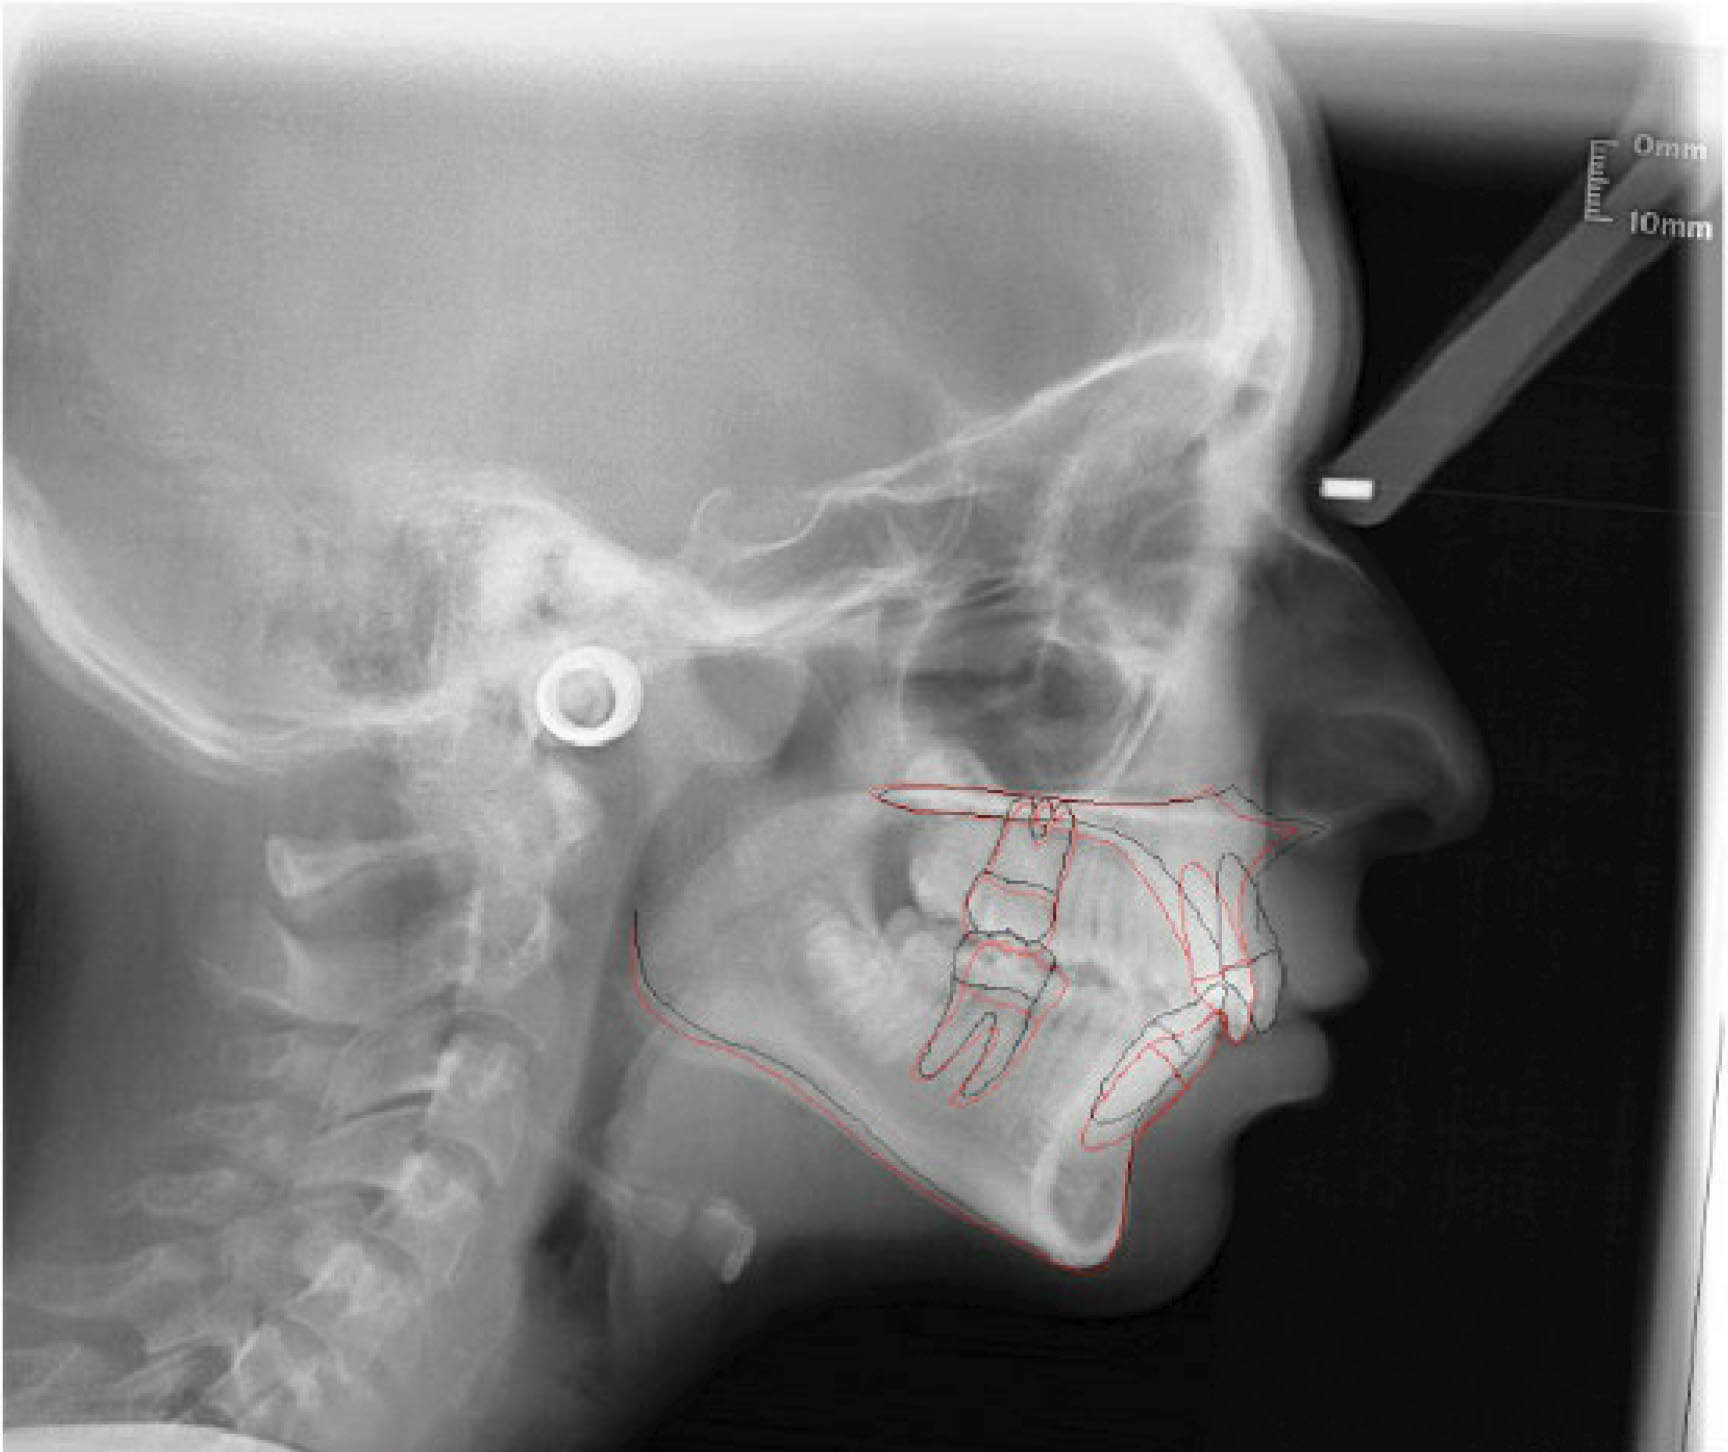

بیمار بعدی دختر ۱۲ ساله در مرحله اواخر میکس دنتیشن (شکلهای 92-۶ الی 94-۶) با اکلوژن ClII/1 است، دیپ بایت و کرادینگ دو فک دارد و لینگوالی شدن دندانهای قدامی بالا و پایین مشخص است. در (شکل 92-۶) هر دو لترال پایین را مشاهده میکنید که بلاک شدهاند. در OPG چیز خاصی مشاهده نمیشود و در لترال سفالومتری ارتفاع عمودی صورت کمی کاهش یافته و انسیزورها رترود شدهاند.

شکل 92-6

شکل 93-6

شکل 94-6

در انتهای درمان هم کرادینگ خوب درمان شد و هم رابطه مولری درست گردید (شکلهای 95-۶ الی 97-۶). عکس OPG طبیعی و سوپرایمپوز نمودن عکسهای لترال سفالومتری نشاندهنده پروترود شدن انسیزورهای بالا و پایین میباشد.

نکته: همانطور که در مقالات در اول مبحث بیان شد، موقعیت مولر بالا و نقطه A در طول درمان فرقی نمیکند. این تغییرات مانند استفاده از هدگیر است در حالیکه با الاستیک کلاسII بدست آوردهایم. ضمناً رشد مندیبل و قدامیتر قرار گرفتن نقطه پوگونیون هم مشخص میباشد و منجر به کاهش تحدب صورت گردیده است.

نتیجه: طول درمان ۲۸ ماه با دو قالبگیری مجدد و الاستیک کلاسII ۲ انسی بود.